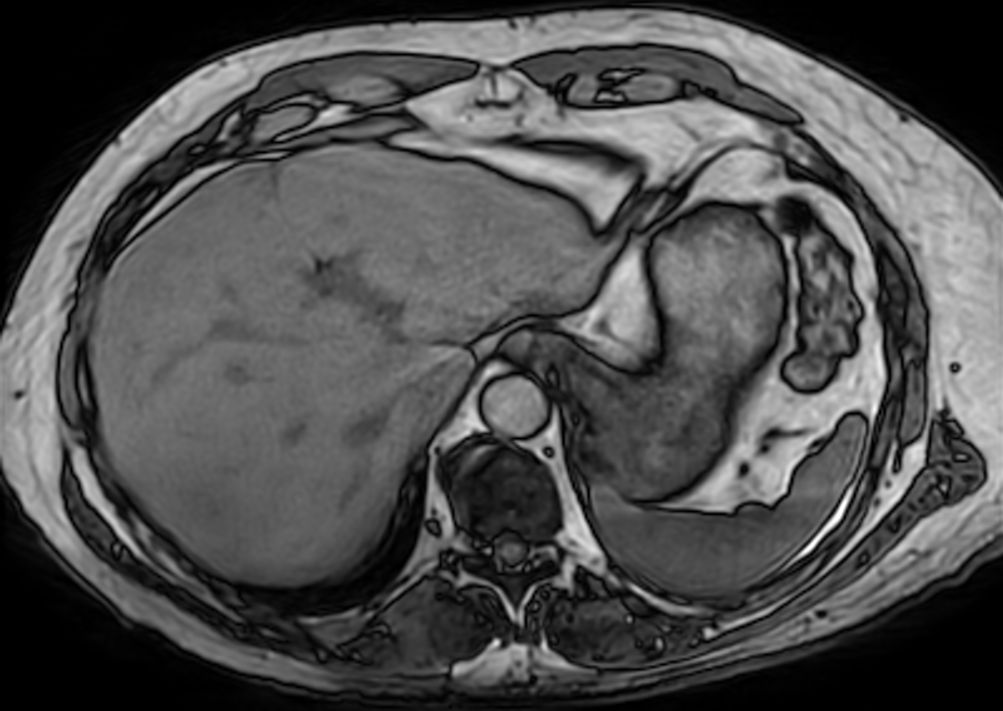

Axial T2w TSE mDIXON (water only)SmartSpeed MotionFree